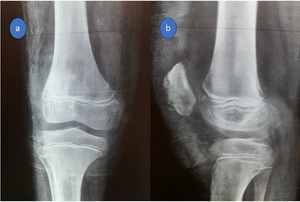

Investigations

At the emergency room, standard AP and lateral radiographs were performed, which revealed patella alta as well as a small osteochondral fragment at the inferior pole of the patella. (Figure 7). As a result of these radiographic findings, a patellar sleeve fracture was diagnosed.